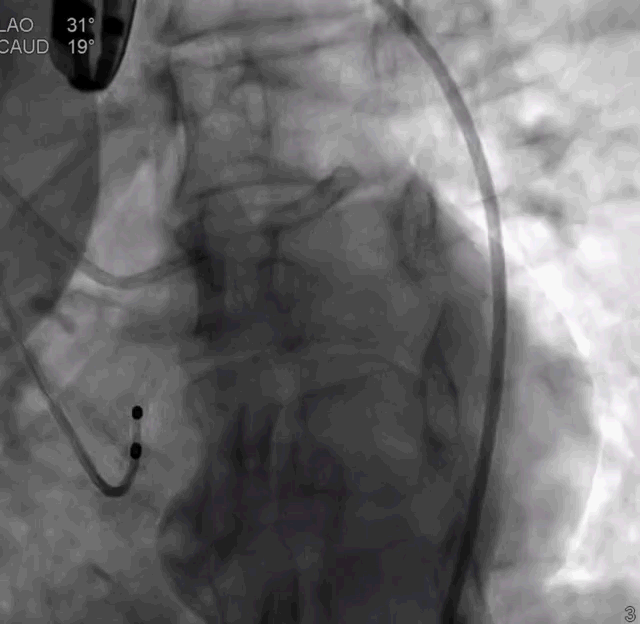

TaurusOne®轻松过弓

TaurusOne®释放过程:

瓣膜定位

瓣膜释放后形态位置良好,造影无返流